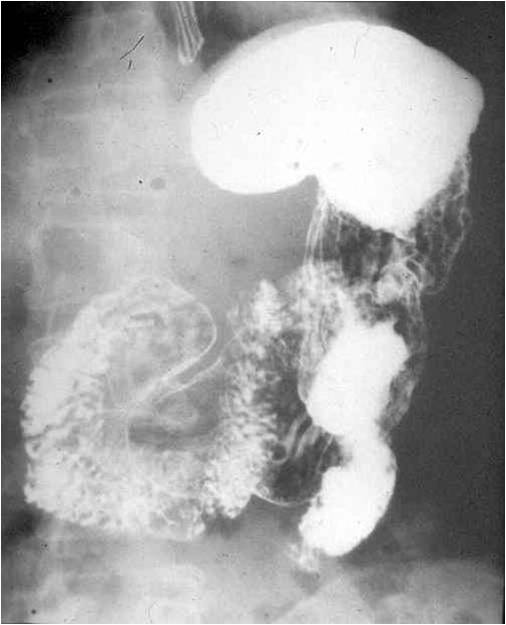

Image

Fig.18.: Scirrhus

Radiographic findings: Generally, the lesion starts in the antrum. In the beginning it does not produce any overt symptoms other then parietal stiffness, until the infiltrative tumor spread remains confined to the gastric wall and does not involve the mucosa. Endoscopy can suggest altered wall motility. This can be verified on the upper GI series. The affected wall segment does not show peristaltic activity. The relief of the lesser curvature has a serrated appearance, and wall stiffness could expand to the entire stomach. The stomach morphology transforms into a tube like configuration, while the gastric size is shrunken.